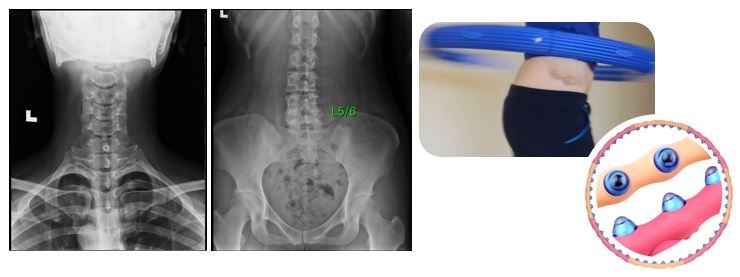

엑스레이 판독 수업 때 교수님께서 제 엑스레이를 보시고 척추가 심하게 비틀려있고 로테이션 되있다고 혹시 무용하셨냐고 물어보셨었는데요...

저는 그때 무용이랑은 전~~혀 무관한 삶을 살아서 정말 많이 당황했었습니다.

엑스레이 찍으러 병원에 간 것도 처음이었고, 제 척추를 보는 것도 처음이었는데, 생각보다 심각하게 말씀하셔서 몇일간 우울해했었습니다.

이 날 집에오는 버스안에서 곰곰이 생각해보니까 제가 어렸을 때 일명 이영자 훌라후프라고, 지압 훌라후프 다들 아시죠? 이거를 하면 이영자처럼 살이 정말 빠지는 줄 알고 거의 매일 하루에 30분~1시간 정도씩 십몇년을 돌렸었는데 이 것 때문에 제 척추가 저렇게 로테이션 된 게 아닌가 생각해 봤습니다

이 날 집에오는 버스안에서 곰곰이 생각해보니까 제가 어렸을 때 일명 이영자 훌라후프라고, 지압 훌라후프 다들 아시죠? 이거를 하면 이영자처럼 살이 정말 빠지는 줄 알고 거의 매일 하루에 30분~1시간 정도씩 십몇년을 돌렸었는데 이 것 때문에 제 척추가 저렇게 로테이션 된 게 아닌가 생각해 봤습니다.